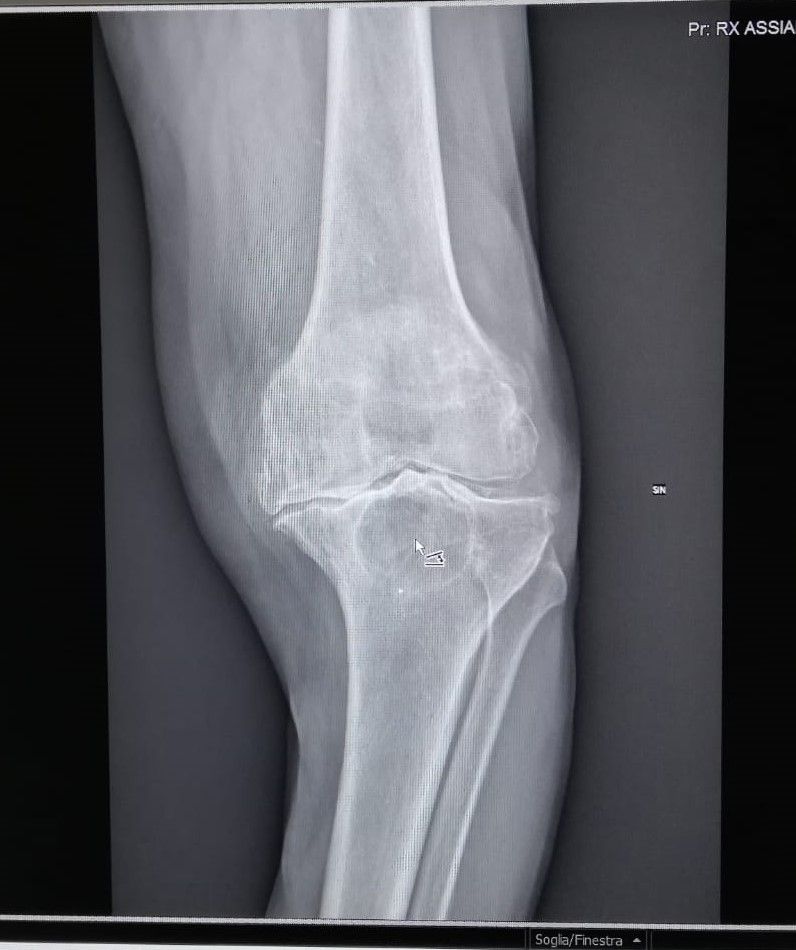

- Gonartrosi (Artrosi del ginocchio)

- osteonecrosi

• Artrosi

• Osteoartrosi

• gonartrosi (artrosi del ginocchio)

• Osteonecrosi